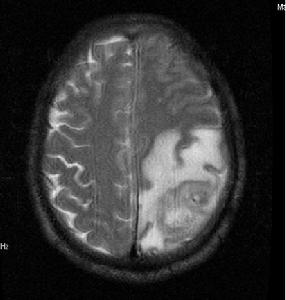

9、磁共振成像(MRI)是近年套用於臨床的新檢查方法。在腦炎期病灶呈邊緣不清的高信號改變,中心壞死區為低信號改變,T2(橫弛豫時間)延長,周邊腦水腫也呈高信號變化,灰白質對比度消失,T1(縱弛豫時間)和T2也延長。腦炎晚期的病灶中央低信號區擴大,IR(反向復原)成像示中央區仍為低強度。包膜形成期的中央區低信號,T1延長,但在長TR(重複時間)成象時原低信號變成較腦脊液高的高信號。包膜則為邊界清楚的高信號環。鄰近腦灰白質對比度恢復正常,但T1,T2仍輕度延長。因此MRI顯示早期腦壞死和水腫比CT敏感,區分膿液與水腫能力比CT強,但在確定包膜形成,區分炎症與水腫不及CT敏感。

5、電子計算機斷層腦掃描(CT)及磁共振成像檢查(MRI):自從CT及MRI用於臨床,對顱內疾患,尤其占位病變的診斷有了重大突破。CT可顯示腦膿腫周圍高密度環形帶和中心部的低密度改變。MRI對膿腫部位、大小、形態顯示的圖像信號更準確。由於MRI不受骨偽影的影響,對幕下病變檢查的準確率優於CT。CT和MRI能精確地顯示多發性和多房性腦膿腫及膿腫周圍組織情況。